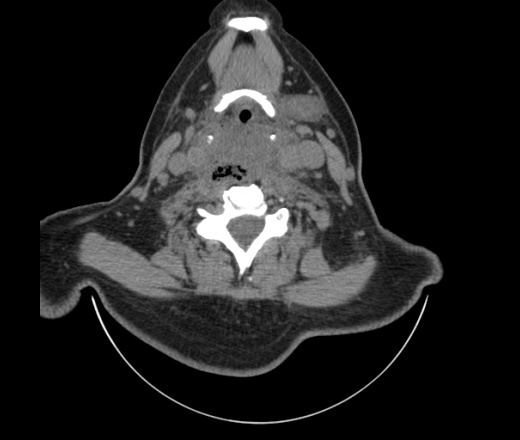

Женщина поступила в х/о спустя 4 дня после того как при употреблении карася подавилась костью.

Наличие газа в средостении на протяжении тел С2-С6 (медиастинальна эмфизема); рыбная кость на уровне тела С6.

Согласен с Вами; конечно, наличие газа в клетчатке ретрофарингеального пространства (затмение с опечаткой..). К сожалению, процесс "продвигается" к медиастиниту. Но почему никто, не отмечает наличие рыб. кости; или это для Всех очевидно?

Так вы уже отметили. Хотя ориентировал бы не скелетотопически, а на перстнечерпаловидный сустав.

Кость то мы сразу выявили, размеры где то 17*2мм, но ее так и не получается найти в этой каше